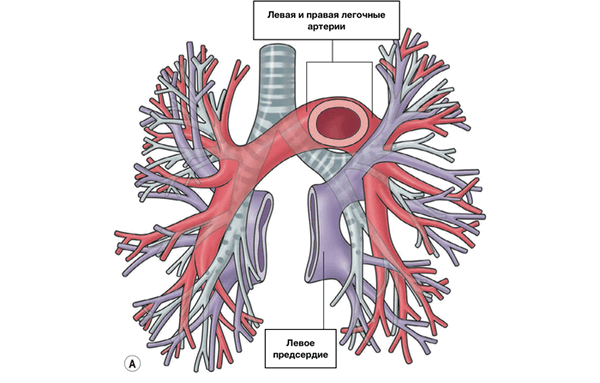

Кровоснабжение легких обеспечивается двумя системами: легочной артерией и бронхиальными артериями, а также двойной системой венозного дренажа, через легочные и непарные вены. Внутри легких ветви легочной артерии (ЛА) сопровождают соответствующие бронхи и разветвляются вместе с ними вплоть до бронхиол. Добавочные, не связанные с бронхами ветви проникают непосредственно в паренхиму.

ЛЕГОЧНЫЕ ВЕНЫ

Из капилляров легкого начинаются венулы, которые сливаются в более крупные вены и в каждом легком формируют по две легочные вены.

Из двух правых легочных вен больший диаметр имеет верхняя, так как по ней оттекает кровь от двух долей правого легкого (верхней и средней). Из двух левых легочных вен больший диаметр имеет нижняя вена. В воротах правого и левого легких легочные вены занимают их нижнюю часть. В задней верхней части корня правого легкого расположен главный правый бронх, кпереди и книзу от него — правая легочная артерия.

У левого легкого сверху находится легочная артерия, кзади и книзу от нее — левый главный бронх. У правого легкого легочные вены лежат ниже артерии, следуют почти горизонтально и на своем пути к сердцу располагаются позади верхней полой вены, правого предсердия и восходящей части аорты. Обе левые легочные вены, которые несколько короче правых, находятся под левым главным бронхом и направляются к сердцу также в поперечном направлении, кпереди от нисходящей части аорты. Правые и левые легочные вены, прободая перикард, впадают в левое предсердие (их конечные отделы покрыты эпикардом).